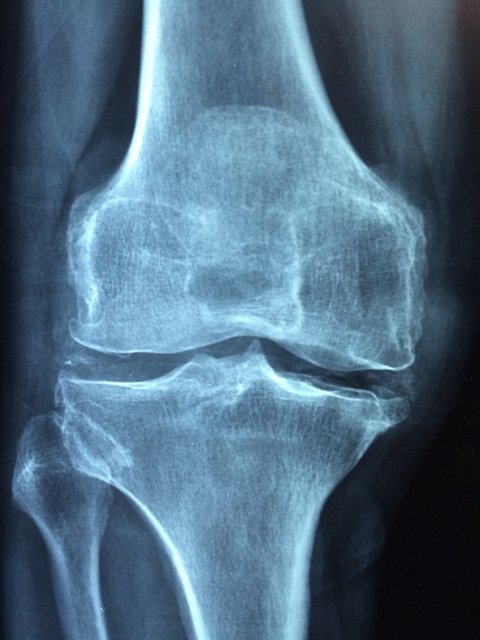

퇴행성 관절염이란 나이 들어가면서 연골이나 뼈와 인대 등이 점차 손상되어 염증과 통증을 일으키는 질환으로 이차성 퇴행성 관절염은 관절연골에 손상을 줄 수 있는 외상, 질병 및 기형이 원인이 되는 것으로 세균성 관절염이나 결행성 관절염 후 관절연골이 파괴된 경우, 심한 충격이나 반복적인 가벼운 외상후 발생하기 쉬운 것으로 알려져 있습니다.

퇴행성 관절염 초기 증상

- 통증 : 관절이 아프고 붓습니다. 열감이 나기도 합니다.

- 뻣뻣함 : 관절이 뻣뻣해지고 움직임이 불편해집니다. 이러한 증상은 특히 아침에 일어났을 때 심하게 나타나며 시간이 지나며 완화가 됩니다.

- 소리 : 관절을 움직일 때 소리가 나기도 합니다.

- 기능 장애 : 관절이 아프고 움직이기 어려워서 일상생활에 지장이 생기기도 합니다.